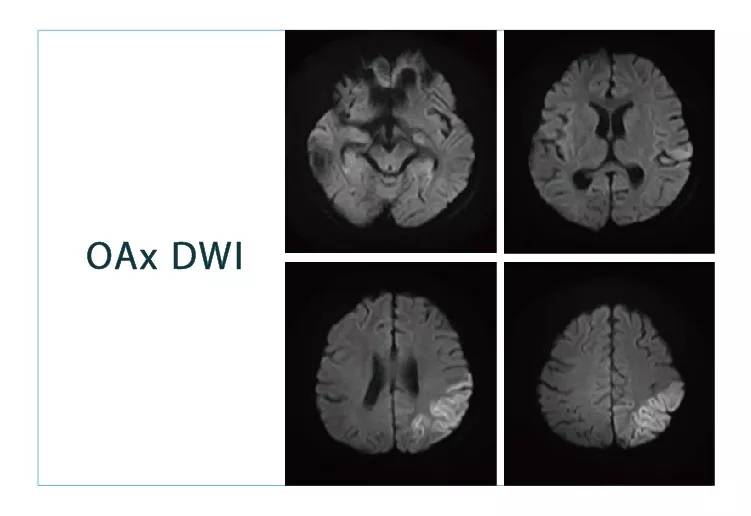

【朗润影像档案】20180817磁共振影像病例结果讨论